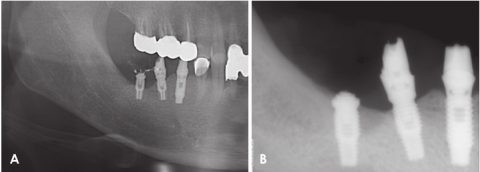

图2.A.全景片局部影像显示左侧下颌磨牙的根尖周放射可透性。B.全景片影像显示拔牙后约4个月植入种植体。

图3.A.全景片显示从左下前磨牙到第二磨牙有不清楚的渗透性骨质破坏。与图2A相比,病变已扩展至下颌管。B.根尖片可见浸润性骨质破坏和增大的软组织阴影(箭头)。